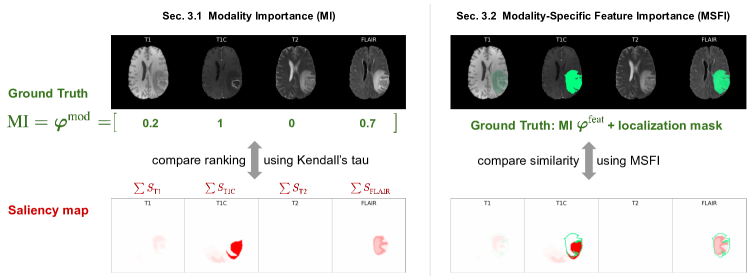

In this work, we give an exploratory answer to this question by proposing evaluation methods and conducting extensive comparisons with 16 commonly used saliency map methods. Specifically, we propose two evaluation methods/metrics, Modality Importance (MI) and Modality-Specific Feature Importance (MSFI), that reflect clinical knowledge on interpreting multi-modal medical images. The first metric, MI, corresponds to clinicians’ prioritization of multiple modalities. It uses Shapley value (Shapley, 1951) to determine the ground-truth importance for each image modality, and compares modality-wise summations of saliency map values with such a ground-truth. The second metric, MSFI, measures fine-grained clinical requirement on localizing features that are specific to each modality. It combines MI with feature localization masks as the ground-truth, and calculates the ratio of saliency map regions inside the segmentation map, weighted by MI. With the two metrics and a clinician user study, we conducted extensive evaluations on 16 saliency map methods that cover the most common activation-, gradient-, and perturbation-based approaches. The findings show that most saliency map methods can reflect the importance of a modality as a whole, but only a few methods could capture the modality-specific fine-grained features that meet clinical needs (Fig. 2). Our contributions in this work are:

3 Methods to Evaluate Multi-Modal Saliency Map Explanations

The overarching goal of the evaluation is to examine whether a saliency map method can reliably reveal features on multi-modal medical images that are clinically meaningful, given a well-trained model. Based on our physician user study (Section 4), we abstract such goal as two specific clinical requirements: modality prioritization, and modality-specific feature localization, which correspond to our evaluations at two granularity levels: 1) Modality Importance: it measures a model’s overall importance of each modality as a whole; and 2) Modality-Specific Feature Importance (MSFI): it measures how well the saliency map can localize the modality-specific important features on each modality. Fig. 3 outlines the evaluation methods.

3.1 Modality Importance (MI)

Evaluation

To compare the saliency maps’ modality importance value with the aforementioned ground-truth, for each saliency map method, we generate and post-process (Section 5.2) the saliency maps, and calculate the estimated modality importance as the sum of all positive values of the saliency map for that modality. MI Correlation measures the MI ranking agreement between the ground-truth and the estimated MI, calculated using Kendall’s Tau-b correlation on the test set.

3.2 Modality-Specific Feature Importance (MSFI)

The above Modality Importance prioritizes the important modality, but it is a coarse measurement and does not examine the particular image features within each modality. To inspect the fine-grained features within each modality image, we further propose the MSFI (Modality-Specific Feature Importance) metric. It combines two types of ground-truth information: the modality prioritization information MI, and the feature localization masks/bounding boxes. MSFI is the portion of saliency map values inside the ground truth feature localization mask for each modality, weighted by the normalized MI value φmsubscript𝜑𝑚\varphi_{m}.